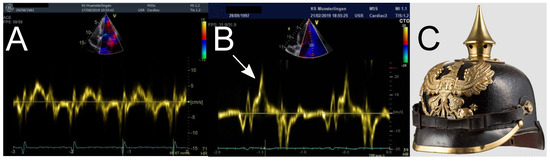

Arrhythmic Mitral Valve Prolapse

by Fritz Widmer

About 1-3% of the general population are aected by mitral valve prolapse. It is dened as a >2 mm superior displacement of the mitral valve leaet(s) during systole with or without mitral regurgitation [...] Full article